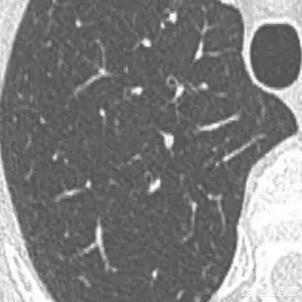

L'étape suivante consiste à déterminer la nature bénigne ou maligne des nodules pulmonaires. Les nodules bénins ne sont en aucun cas des ganglions lymphatiques dans les poumons, des tumeurs difformes, des pneumocytomes sclérosants, etc. Les nodules restants sont ceux qui peuvent être bénins ou malins, et le principe général du traitement de ces nodules est de recommander un suivi, avec un délai de révision allant de 3 mois à 1 an, en fonction des spécificités du nodule (morphologie, taille, densité, etc.). Certains nodules peuvent se résorber et disparaître au cours du suivi, comme les nodules inflammatoires, tandis que d'autres peuvent rester inchangés, comme les granulomes, ce qui est une bonne information. Si des signes de malignité apparaissent au cours du suivi, tels que l'élargissement du nodule, l'augmentation des composants réels ou solides dans le nodule de verre dépoli, un nodule plus dense, ou la présence de vaisseaux sanguins périphériques qui se développent, etc. En fait, c'est comme regarder les gens, un visage de droiture est généralement une bonne personne, une mauvaise personne féroce et vicieuse, et certains temporaires ne peuvent être vus que par l'observation du comportement de la personne, si les règles ne sont généralement pas effrayées, et si vous trouvez qu'il y a un mauvais comportement devrait être traité en temps opportun. Figure 1, nodule de verre dépoli dans la partie supérieure du poumon gauche (flèche orange), suivi pendant plus de deux ans sans changement. Figure 2, deux petits nodules de verre dépoli dans la partie supérieure du poumon droit (flèches orange), qui ont disparu après deux ans. Figure 3, nodule en verre dépoli dans la partie supérieure droite du poumon, qui a grossi au cours du troisième suivi, il est recommandé de le traiter positivement, et la pathologie chirurgicale du carcinome in situ, c'est-à-dire des lésions précancéreuses, peut réellement tuer le cancer du poumon dans l'œuf.